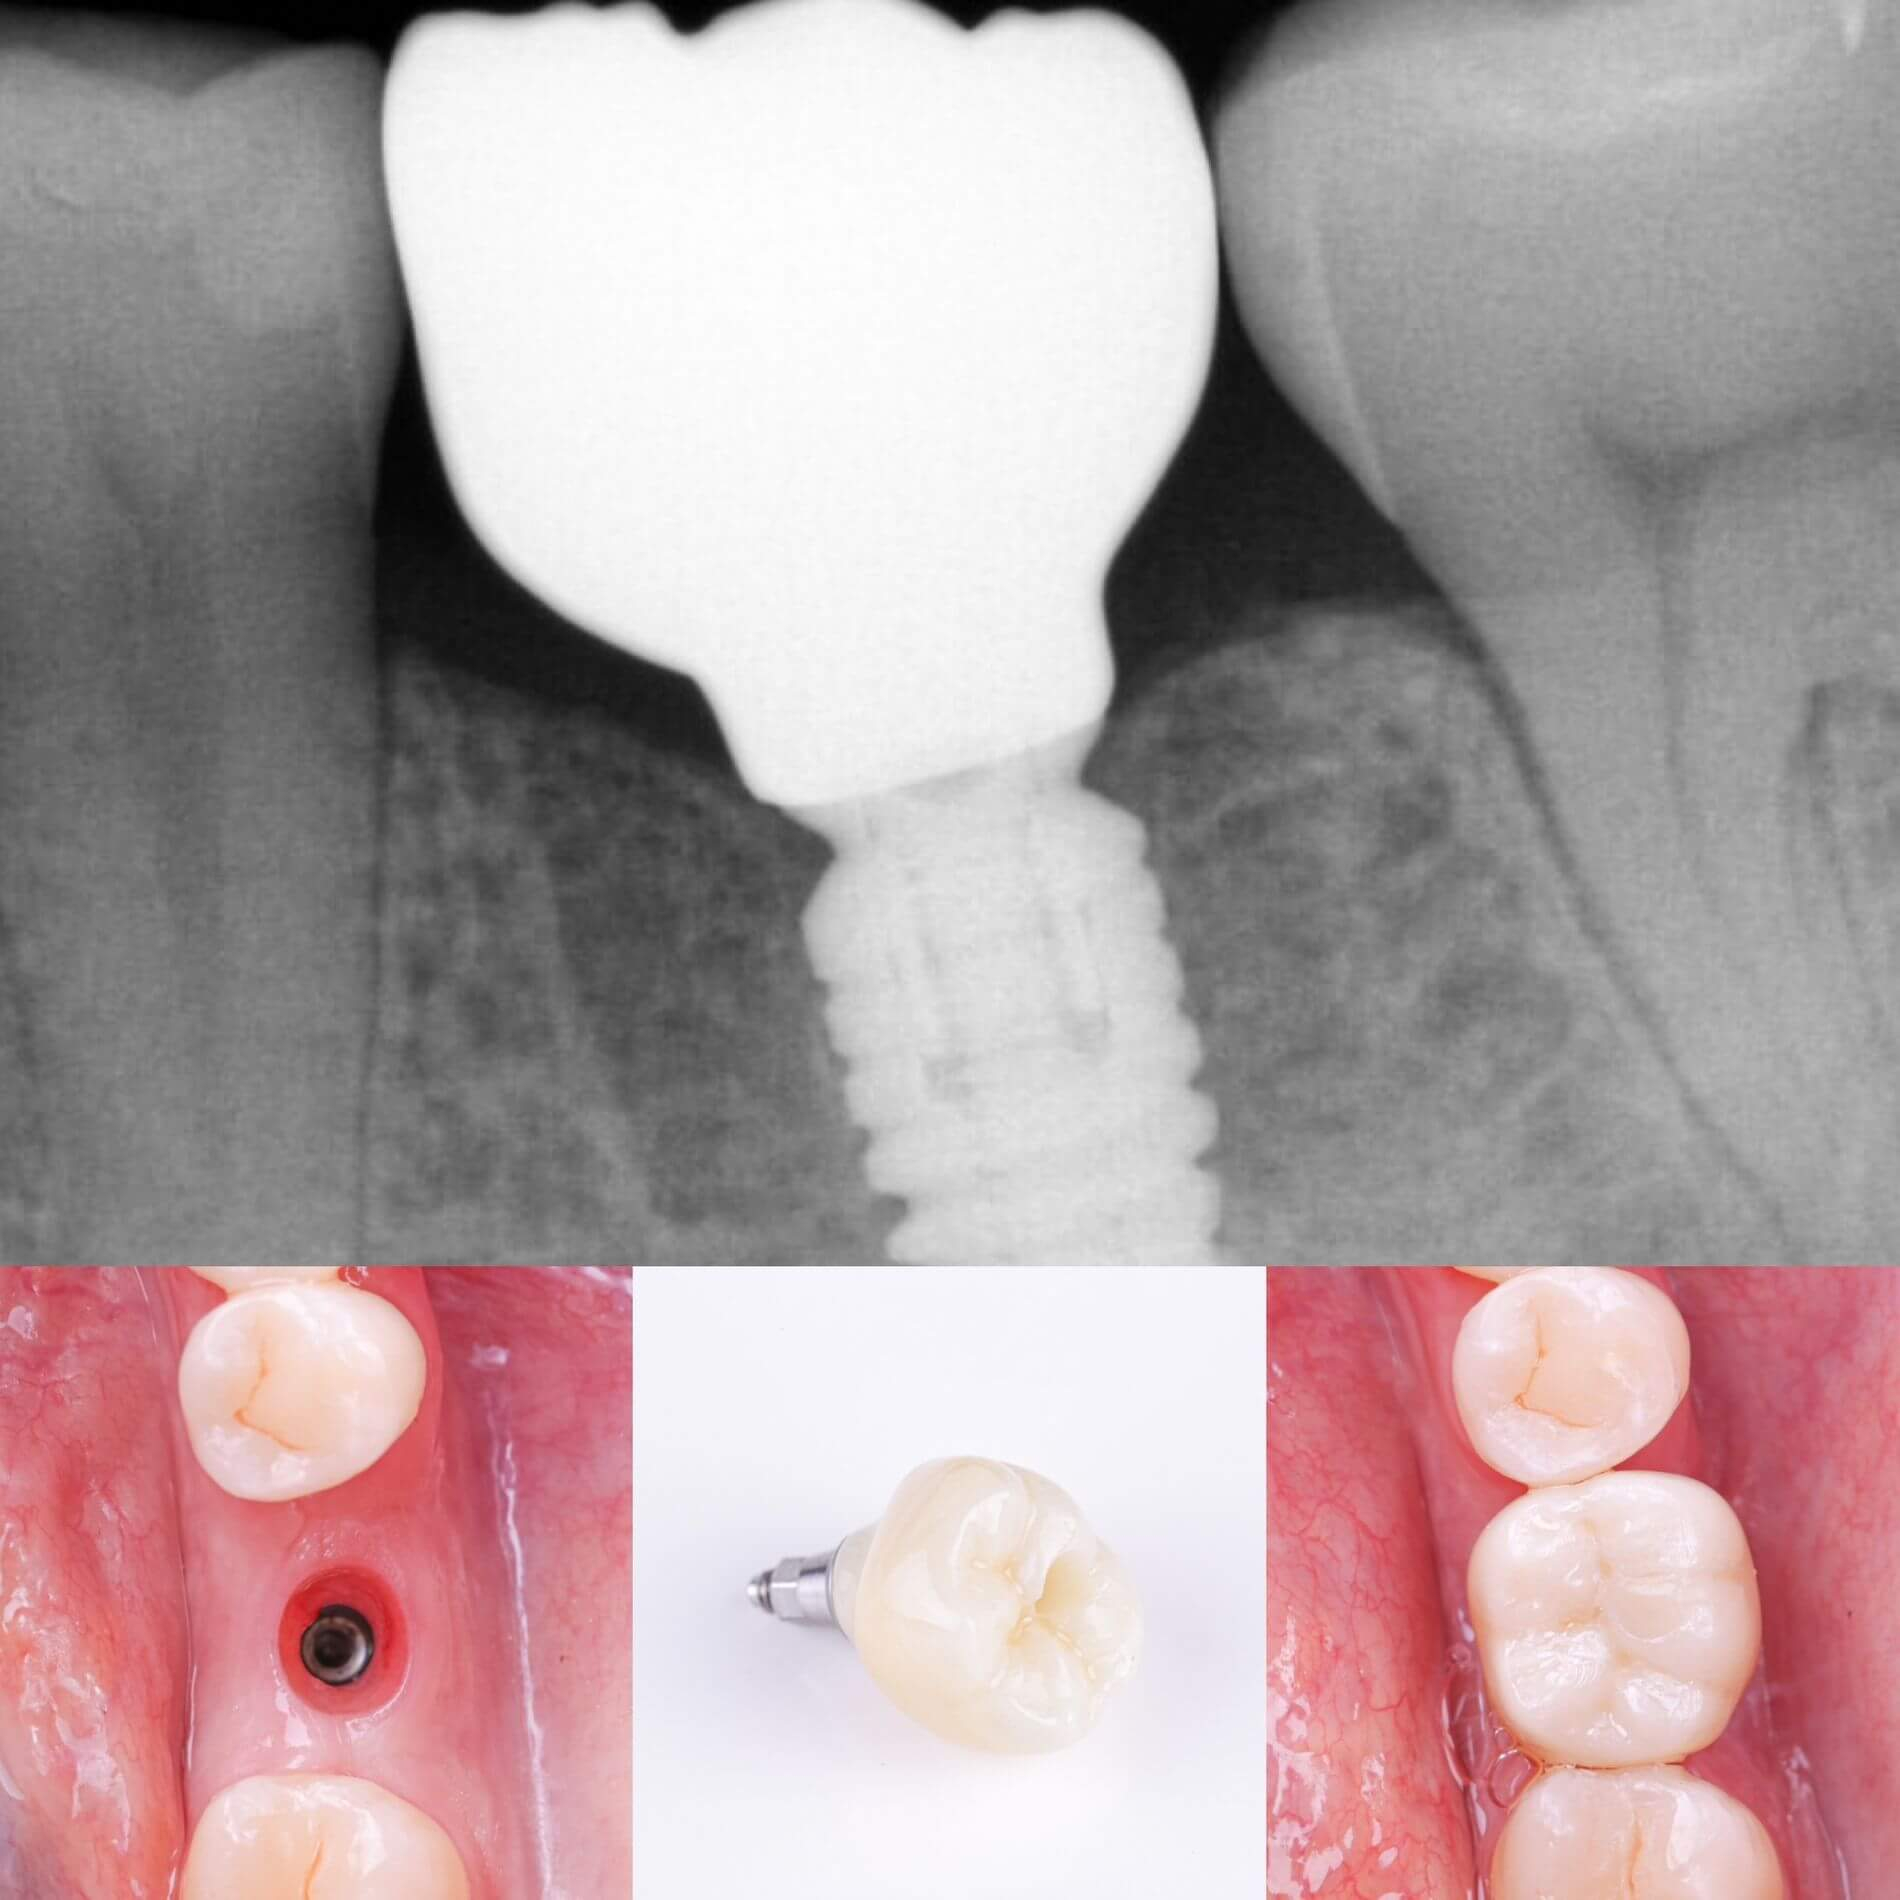

Імплантація - це метод вживлення імплантату (штучного кореня) у верхню або нижню щелепу.Такий штучний корінь виготовляється з спеціального сплаву, що надійно вживлюється в кістку та стає надійною опорою, на яку встановлюється коронка.

- Одноетапна імплантація відбувається за один візит, шляхом встановлення імпланту на місці видаленого зуба. Такий спосіб має свої обмеження: наявність достатнього для імплантації обсягу кістки та відсутність запальних процесів (наприклад, кісти). Коронка виготовляється одночасно з встановлення імпланту;

- Двоетапна імплантація відбувається в два послідовні етапи: спочатку здійснюється встановлення імпланту та витримується термін його повної остеоінтеграції (2-4 місяці, в залежності від щелепи), після чого встановлюється коронка;

- кріплення абатменту та коронки;